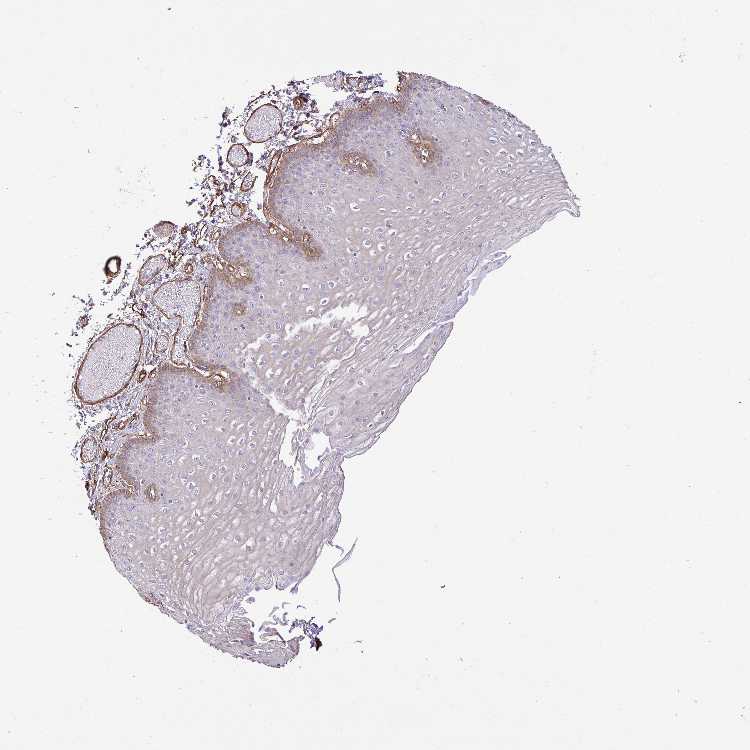

ESOPHAGUS - Antibody stainingi

Antibody staining in the annotated cell types in the current human tissue is reported as not detected, low, medium, or high, based on conventional immunohistochemistry profiling in selected tissues. This score is based on the combination of the staining intensity and fraction of stained cells.

Each image is clickable and will lead to virtual microscopy that enables deeper exploration of all samples and also displays staining intensity scores, fraction scores and subcellular localization as well as patient and tissue information for each sample.

Antibody HPA054822

Squamous epithelial cells Medium